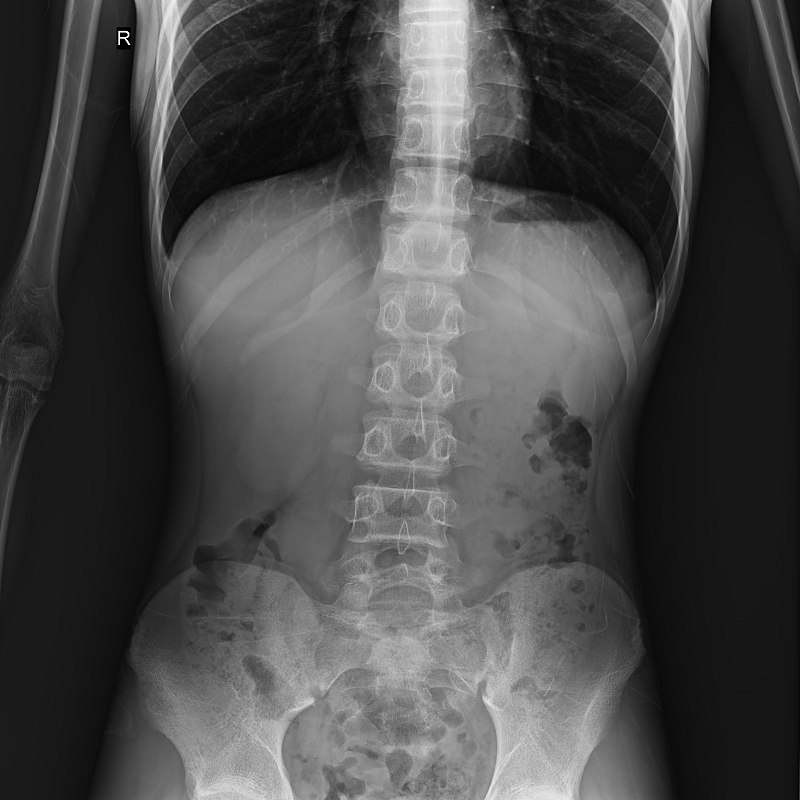

●呈現(xiàn)全下肢或全脊柱圖像

●在脊柱及下肢畸形矯正手術(shù)治療中,為術(shù)前方案制定和術(shù)后復(fù)查提供精準(zhǔn)測(cè)量

●有效解決傳統(tǒng)X光片不能一次成像問題,為患者提供更加優(yōu)質(zhì)的醫(yī)療服務(wù)

點(diǎn)片裝置可實(shí)現(xiàn)大范圍縱向移動(dòng),高效完成各部位、全身拼接等檢查需求